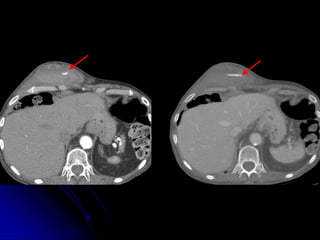

• Demonstrate complexities that

comorbidities/incidental findings pose in

imaging evaluation

INCIDENTAL

FINDINGS &

COMORBIDITIES

COMMUNICATION